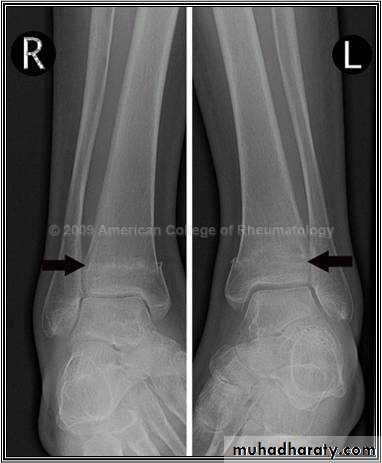

3. Stress fractures

Fatigue or stress fractures can occur in metal and other materials due to gradual rearrangement of molecular structure which weaken the metal and permit the crack to occur.

A similar mechanism of crack can occur in bone.

These fractures occur in Normal bone which is subject to repeated stress, typically seen in athletes or military personnel.

This is most seen in tibia, fibula and metatarsal.

The great difference between stress and traumatic fractures is that there is no single specific injury in case of fatigue fractures, the onset of pain is gradual and increase by activity and relieved by rest.

Examination reveals local tenderness over the affected bone. X-ray finding may be normal at first time and after 2-4 weeks the radiological changes appear as a faint hairline crack surrounded by callus, occasionally if a biopsy taken from the callus may be mistaken to diagnosed as a bone sarcoma!!!!). A mistake that should not occur if the feature of stress fracture are properly understood.

Treatment: rest + non-steroidal anti inflammatory drugs